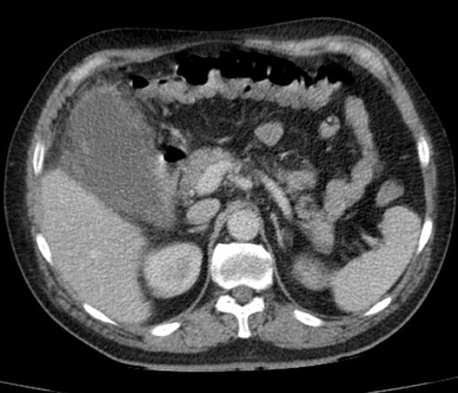

Image radiologique TDM

, contrast intraveineuse en coupe coronal : Se

presente une cholecystite aigue avec deux

calculs de la vesicule biliaire . Sa paroi est

epais , oedeme |